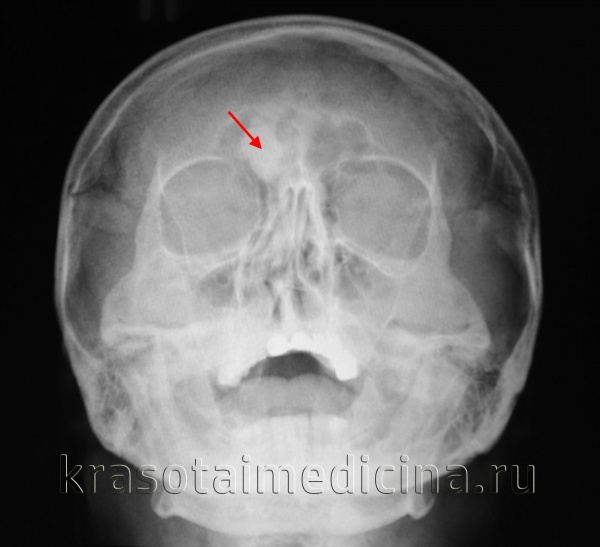

(Слева) На рентгенограмме в прямой проекции определяется классическая компактная остеома в нижних внутренних отделах правой лобной пазухи в остальном хорошо пневматизированной.

(Справа) На аксиальной КТ в костном окне определяется плотная компактная остеома правой лобной пазухи, пересекающая срединную линию, рас пространяющаяся влево и интракраниальною обеих лобных пазухах присутствует «запертый» секрет. Остеомы чаще обнаруживаются в лобных пазухах, чем в любых других. (Слева) На аксиальной КЛКТ определяется губчатая остеома передней стенки правой верхнечелюстной пазухи. Остеома состоит из ядра, представленного губчатой костью, покрытого толстой и ровной кортикальной пластинкой.

Рентгенологические признаки остеомы придаточных пазух носа патогномоничны для этой опухоли. На рентгенограмме легко обнаруживается очень интенсивная, равномерной плотности тень с резкими, отчетливыми, большей частью неправильными контурами. Помимо рентгенологического обнаружения остеомы, всегда необходимо определять ее топографическое расположение в пазухе и место прикрепления ножки. Этой цели чаще всего можно достигнуть путем многоосевой рентгенографии, а в трудных случаях—томографии. Для уточнения диагностики при остеомах придаточных пазух носа может быть рекомендована также стереорентгенография.

В связи с частым бессимптомным течением и неспецифической симптоматикой заболевания количество случайно диагностированных остеом при компьютерной томографии (КТ) носа и околоносовых пазух достигает 1-3% [3, 31]. На К.Т. опухоль обычно представлена плотной гомогенной массой с резкими, отчетливыми контурами [1, 22]. В связи с тем, что очертания опухоли совпадают с контуром пазухи, не всегда удается установить точку прикрепления новообразования («ножку») к стенке синуса [11]. Точно определить анатомическую локализацию образования позволяет однофотонная эмиссионная КТ, благодаря накоплению 99m Tc-метилендифосфоната [32]. Отмечаются также преимущества магнитно-резонансной томографии при интракраниальном росте новообразования [33].